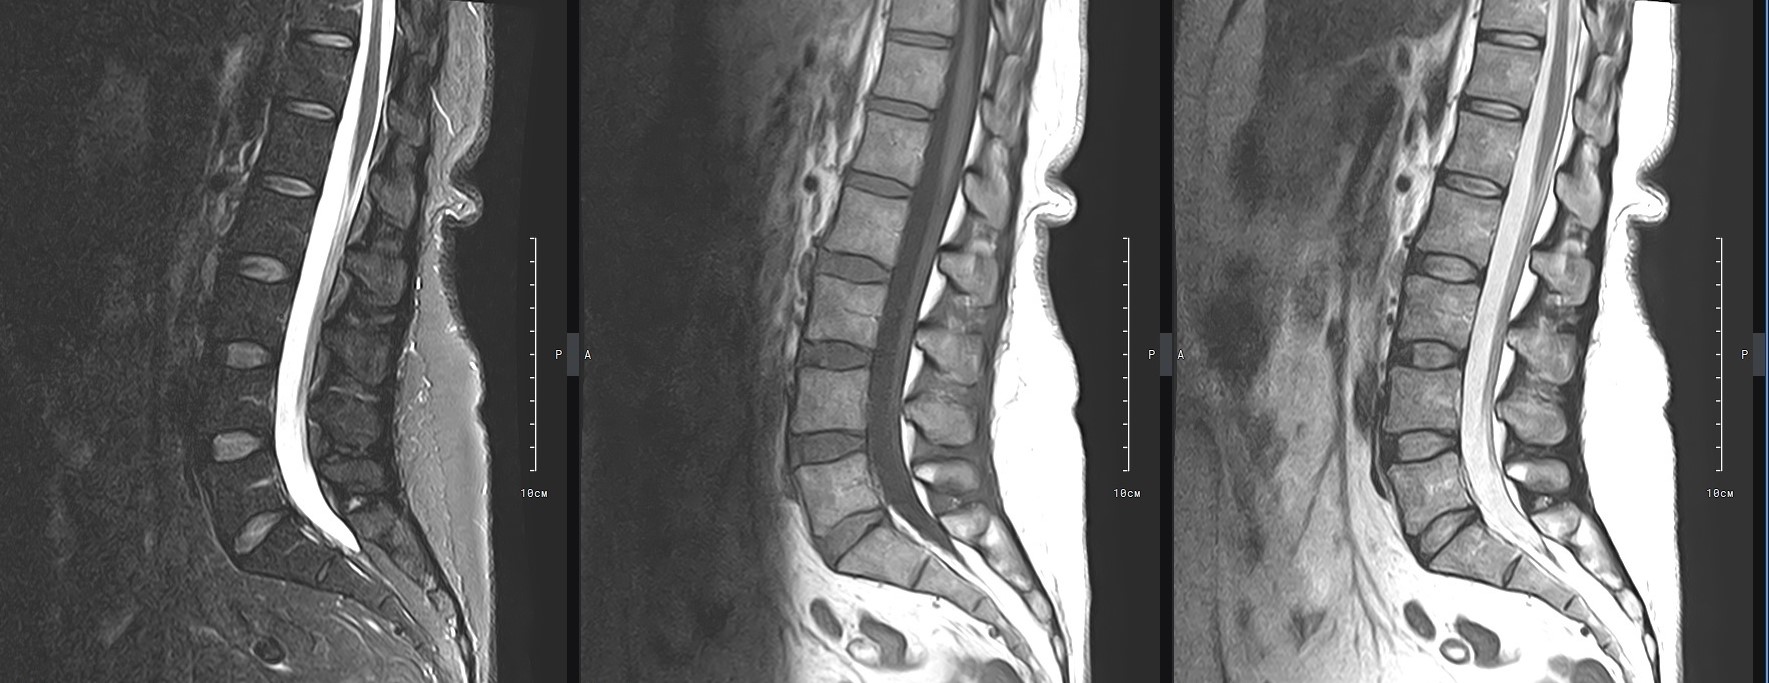

Наиболее точным и эффективным способом диагностики причин появления болей в нижней части спины является МРТ пояснично-крестцового отдела позвоночника. С помощью данного метода можно оценить состояние всех анатомических структур позвоночного столба на исследуемом уровне, безошибочно выявить происхождение болевого синдрома и назначить своевременное лечение.

В клинике «Доступная медицина» диагностика патологии нижней части спины осуществляется на высокотехнологичном оборудовании – новейшем высокопольном томографе TOSHIBA VANTAGE TITAN 1,5 Тесла, который обеспечивает высочайшее качество изображений, точность и достоверность полученных данных. Магнитно-резонансная томография осуществляется без применения ионизирующего излучения, поэтому является безопасным методом обследования и может применяться неоднократно.

Многим пациентам интересно, что показывает МРТ пояснично-крестцового отдела. Высокая детальность получаемых с помощью МР-диагностики изображений позволяет с точностью выявить следующие заболевания, локализующиеся в области поясничного отдела позвоночника:

• протрузии и грыжи межпозвонковых дисков;

• дегенеративные заболевания: остеохондроз, спондилез, спондилоартроз;

• последствия перенесенных травм, такие как компрессионные переломы, подвывихи и смещения позвонков;

• новообразования первичного и вторичного генеза;

воспалительные и деструктивные изменения позвонков и окружающих мягких тканей.